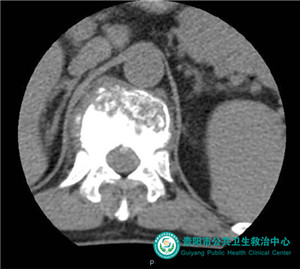

術(shù)后骨水泥充填椎體